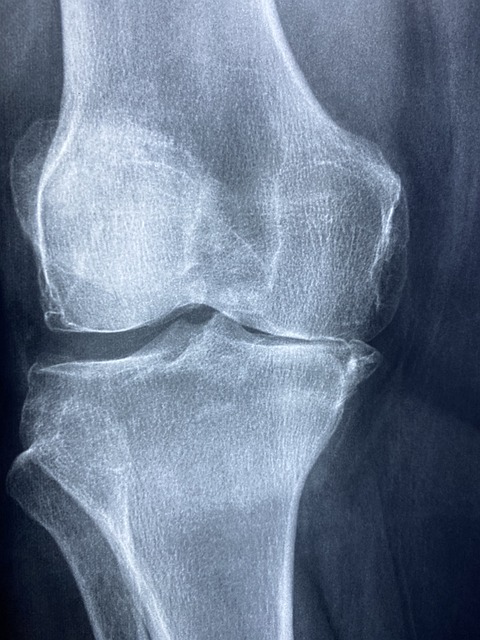

류마티스 관절염의 초기 증상

류마티스 관절염의 초기 증상은 일반적인 관절 통증과 비슷해 많은 사람들이 쉽게 지나칠 수 있습니다.

하지만 증상이 나타난다면 류마티스 관절염을 의심해보고 진료를 받는 것이 좋습니다.

- 양쪽 손목, 양쪽 무릎과 같은 대칭적인 관절에서 통증이 발생합니다.

- 관절의 붓기와 열감

- 통증이 있는 관절 부위가 붓고 만졌을 때 열감이 느껴질 수 있습니다.